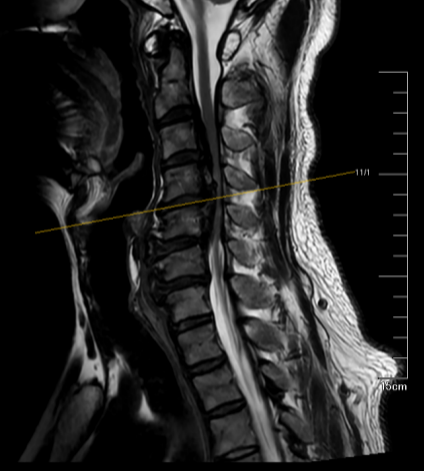

影像检查显示,患者的骨化物节段高、长、厚,脊髓受压严重

Chan先生的病因,是一种被称为颈椎后纵韧带骨化症(OPLL)的疾病。医生告诉他,他颈椎管内原本柔软的保护韧带,在多种原因的作用下发生了骨化,变成了坚硬的骨头,像一块“石头”一样,从前方侵占椎管,将他的脊髓挤压得只剩不到10%的空间。

这在脊柱外科领域,是公认的“难题中的难题”——传统的手术思路是从后方“绕道”,间接扩大空间,期望脊髓能自己往后挪一挪,避开前方的压迫;但这种方法对于Chan先生这样严重的病例来说,就像家门口堵了一块巨石,你不去搬它,反而想把房子往后推,效果可想而知——不仅减压不彻底,脊髓被动后移还可能带来新的损伤。